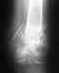

Оскольчатый перелом н/з левой бедренной кости со смещением.Состояние после открытой репарации иммобили

Падение с высоты 12мая,с аппаратом 2месяца, говорят может через месяц снимут. Что скажите Уважаеммые по поводу перелома,как установлен аппарат и как долго с ним быть? спасибо

Оптимальным для подобных переломов является закрытое штифтование с блокированием. Не очень понятно, почему стали лечить именно аппаратом.

По одной проекции в аппарате выглядит неплохо, но неизвестно, как расположены фрагменты на профильной проекции.

Чтобы предположить, как долго быть в аппарате, надо смотреть снимки не только в двух проекциях, но и в динамике. Те. сразу после наложения аппарата, через месяц, через два...